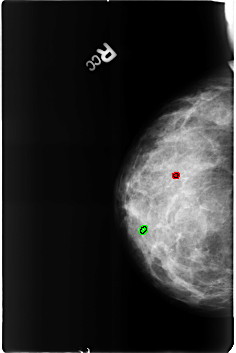

B_3191_1.RIGHT_MLO

RIGHT_MLO LINES 3944 PIXELS_PER_LINE 3032 BITS_PER_PIXEL 12 RESOLUTION 50 OVERLAY

FILE: B_3191_1.RIGHT_MLO.OVERLAY

TOTAL_ABNORMALITIES 2

ABNORMALITY 1

LESION_TYPE CALCIFICATION TYPE ROUND_AND_REGULAR DISTRIBUTION N/A

ASSESSMENT 2

SUBTLETY 5

PATHOLOGY BENIGN_WITHOUT_CALLBACK

TOTAL_OUTLINES 1

BOUNDARY

ABNORMALITY 2